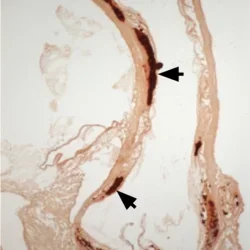

We have discovered expression of bone morphogenetic protein-2 (BMP-2) in human calcific atherosclerotic lesions, which contain bone tissue with complete trabecular bone and marrow.

Atherosclerotic Calcification

We and others have shown the presence of osteochondrogenic cells (arrowhead) in mice on a high-fat diet develop aortic root calcification (arrows).